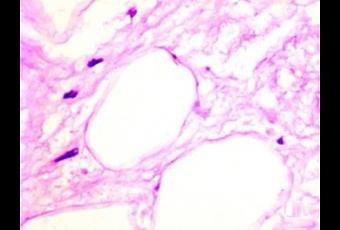

Les mammifères, dont les humains, ont 2 types de tissus adipeux, blanc et brun. Le tissu adipeux blanc (White adipose tissue- WAT), a une faible capacité à brûler l’énergie et est donc associé à un gain de poids et à l’obésité, ainsi qu’à d’autres troubles métaboliques, dont l’hypercholestérolémie, l’hypertension artérielle (HTA) et la résistance à l’insuline (pré-diabète). Combiné à l’excès de poids, cette graisse blanche abdominale est précurseur de syndrome métabolique, un syndrome lié au risque de maladie cardiaque et de diabète.

En revanche, le tissu adipeux brun (Brown adipose tissue- BAT), brûle de l’énergie à un rythme beaucoup plus rapide, dans un processus appelé thermogenèse. En raison de cette consommation accélérée d’énergie, BAT est un terrain de plus en plus privilégié de recherche de nouveaux traitements contre l’obésité. En particulier, l’objectif de pouvoir transformer « WAT » en « BAT » est l’objectif de nombreuses recherches.

En induisant ainsi la graisse blanche à la thermogenèse, le composé GC-1 apporte aux cellules graisseuses la capacité d’éliminer les calories en excès, en les convertissant à la chaleur au lieu de les stocker sous forme de masse adipeuse.